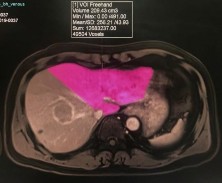

Thể tích gan bảo tồn là một chỉ số không thể thiếu trong phẫu thuật cắt gan lớn, đặc biệt là cắt gan phải và cắt gan thùy phải. Việc tính toán này được thực hiện dựa trên chụp X quang cắt lớp vi tính hoặc chụp cộng hưởng từ.

Hình 1.4. Thể tích gan trái bảo tồn đo bằng chụp cộng hưởng từ (Nguồn: Bệnh viện Đại học Y Dược TP.HCM)